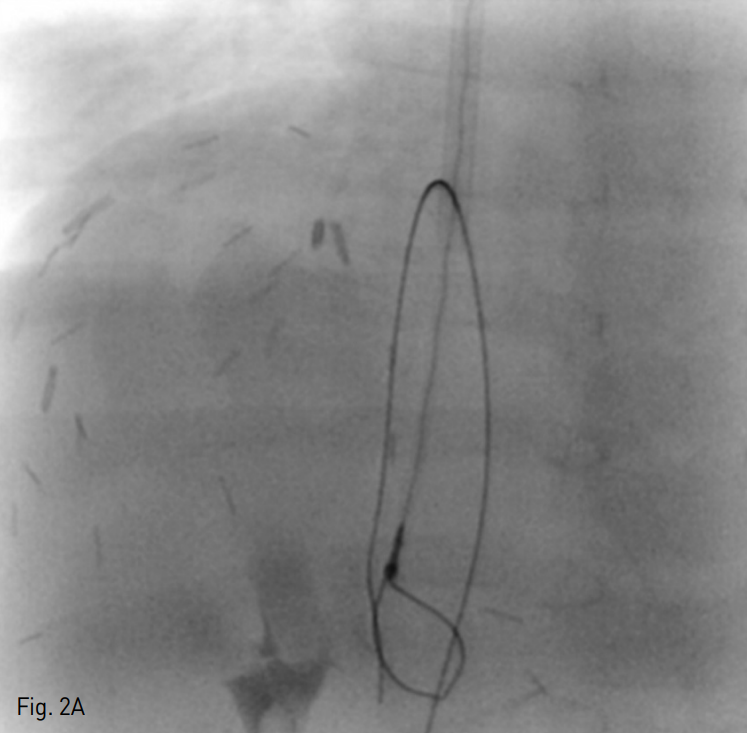

초음파 유도 하에 환자의 우측 내경정맥을 천자한 뒤 혈관초를 삽입하고 5 Fr 혈관조영술용 카테터를 이용하여 간정맥 선택을 시도하였으나 실패하였다. 이어 초음파 유도 하에 22G 천자침을 이용하여 경피경간 경로를 통해 간정맥을 천자한 뒤 0.018 inch 유도철사를 삽입하고 이를 하대정맥까지 진입시켰다. 내경정맥 경로를 통해 올가미형 카테터를 하대정맥까지 진입시킨 뒤 경피경간 경로를 통해 삽입한 유도철사를 잡아 thru-and-thru technique을 이용하여 내경정맥에서 간정맥까지의 경로를 확보하였다 (Fig. 2A). 카테터 진입을 위해 3mm x 40mm 풍선 카테터 (Mustang; Boston Scientific, Natick, MA, USA)를 이용하여 혈관성형술을 시행하고 5 Fr 혈관조영술용 카테터를 삽입한 뒤 간정맥 조영술을 시행하였다. 간정맥 조영술 상 초음파 소견과 유사하게 간정맥 중심부위에 충만결손 병변이 관찰되며 간정맥에서 우심방으로의 조영제 유입은 관찰되지 않았다 (Fig. 2B). 우심방과 간정맥 사이의 압력 차이는 24mmHg로 측정되었다. 간정맥 폐쇄를 해소하기 위해 6mm x 40mm 풍선 카테터 (Mustang)를 이용하여 혈관성형술을 시행하고 다시 시행한 간정맥 조영술에서도 간정맥 폐쇄가 지속적으로 관찰되어 14mm x 30mm 자가확장형 스텐트 (Zilver; Cook, Bloomington, IN, USA)를 삽입하고 8mm x 40mm 풍선 카테터 (Mustang)을 이용하여 다시 혈관성형술을 시행하였다. 이후 시행한 간정맥 조영술 상 간정맥에서 우심방으로의 혈류가 회복되었으며 압력 차이가 5mmHg로 측정되었다 (Fig. 2C).

A. After percutaneous transhepatic access of the occluded hepatic vein, a 0.018-inch guide wire was passed to inferior vena cava and snared with a goose-neck snare catheter to secure access route between the right atrium and the hepatic vein.